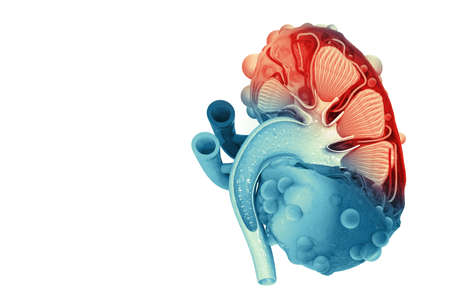

Human kidney cross section on scientific background. 3d illustration

Human kidney cross section on science background. 3d render

Human kidney cross section. 3d illustration

An intricate visualization of a human kidney cross-section, highlighting the vibrant layers of the outer cortex, inner medulla, and intertwining blood vessels agains

Human kidney cross section on scientific background. 3d illustration

Human kidney cross section on scientific background. 3d illustration

Human kidney cross section on scientific background. 3d illustration